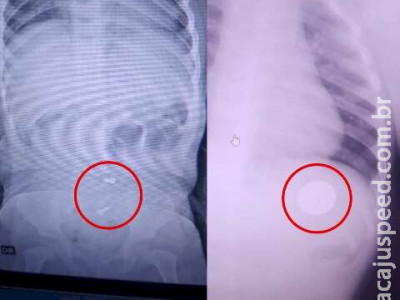

Anthony Davi, um bebê de apenas um ano e quatro meses, enfrenta sérios problemas de saúde após engolir três parafusos e uma moeda de 25 centavos. Inicialmente diagnosticado com pneumonia, ele foi levado à UPA, onde um raio-x revelou os objetos estranhos em seu estômago. Após várias idas ao hospital e um diagnóstico incorreto, a situação de Anthony se agravou, resultando em sangramentos. A família expressou preocupação com a demora no atendimento médico e a falta de acompanhamento adequado, o que pode agravar ainda mais a condição do bebê.

Junto de sua mulher, Ismael levou o filho à UPA (Unidade de Pronto Atendimento) durante a noite do dia 26 de dezembro, quando a criança começou a passar mal. No local foi realizado um raio-x, mas a médica que atendeu o bebê deu diagnóstico de pneumonia e os mandou para casa com uma receita para tratar a criança.

No dia 30 de dezembro, Anthony continuou passando mal e a família retornou à UPA. No local foi feito outro raio-x, mas dessa vez o diagnóstico foi outro. A médica que atendeu a criança na segunda vez verificou que haviam “corpos estranhos' no estômago do bebê. Desta vez, os pais saíram com um encaminhamento para realizar endoscopia no Hospital Regional de Campo Grande.

Apenas no dia 2 de janeiro, após receber outro encaminhamento, Anthony passou pelo procedimento no hospital. “Eles liberaram a gente para ir para casa e passado alguns dias ele ficou ruim de novo. Nós decidimos levar ele para bater um raio-x de novo e descobrimos que ainda havia dois parafusos na barriga dele', contou.